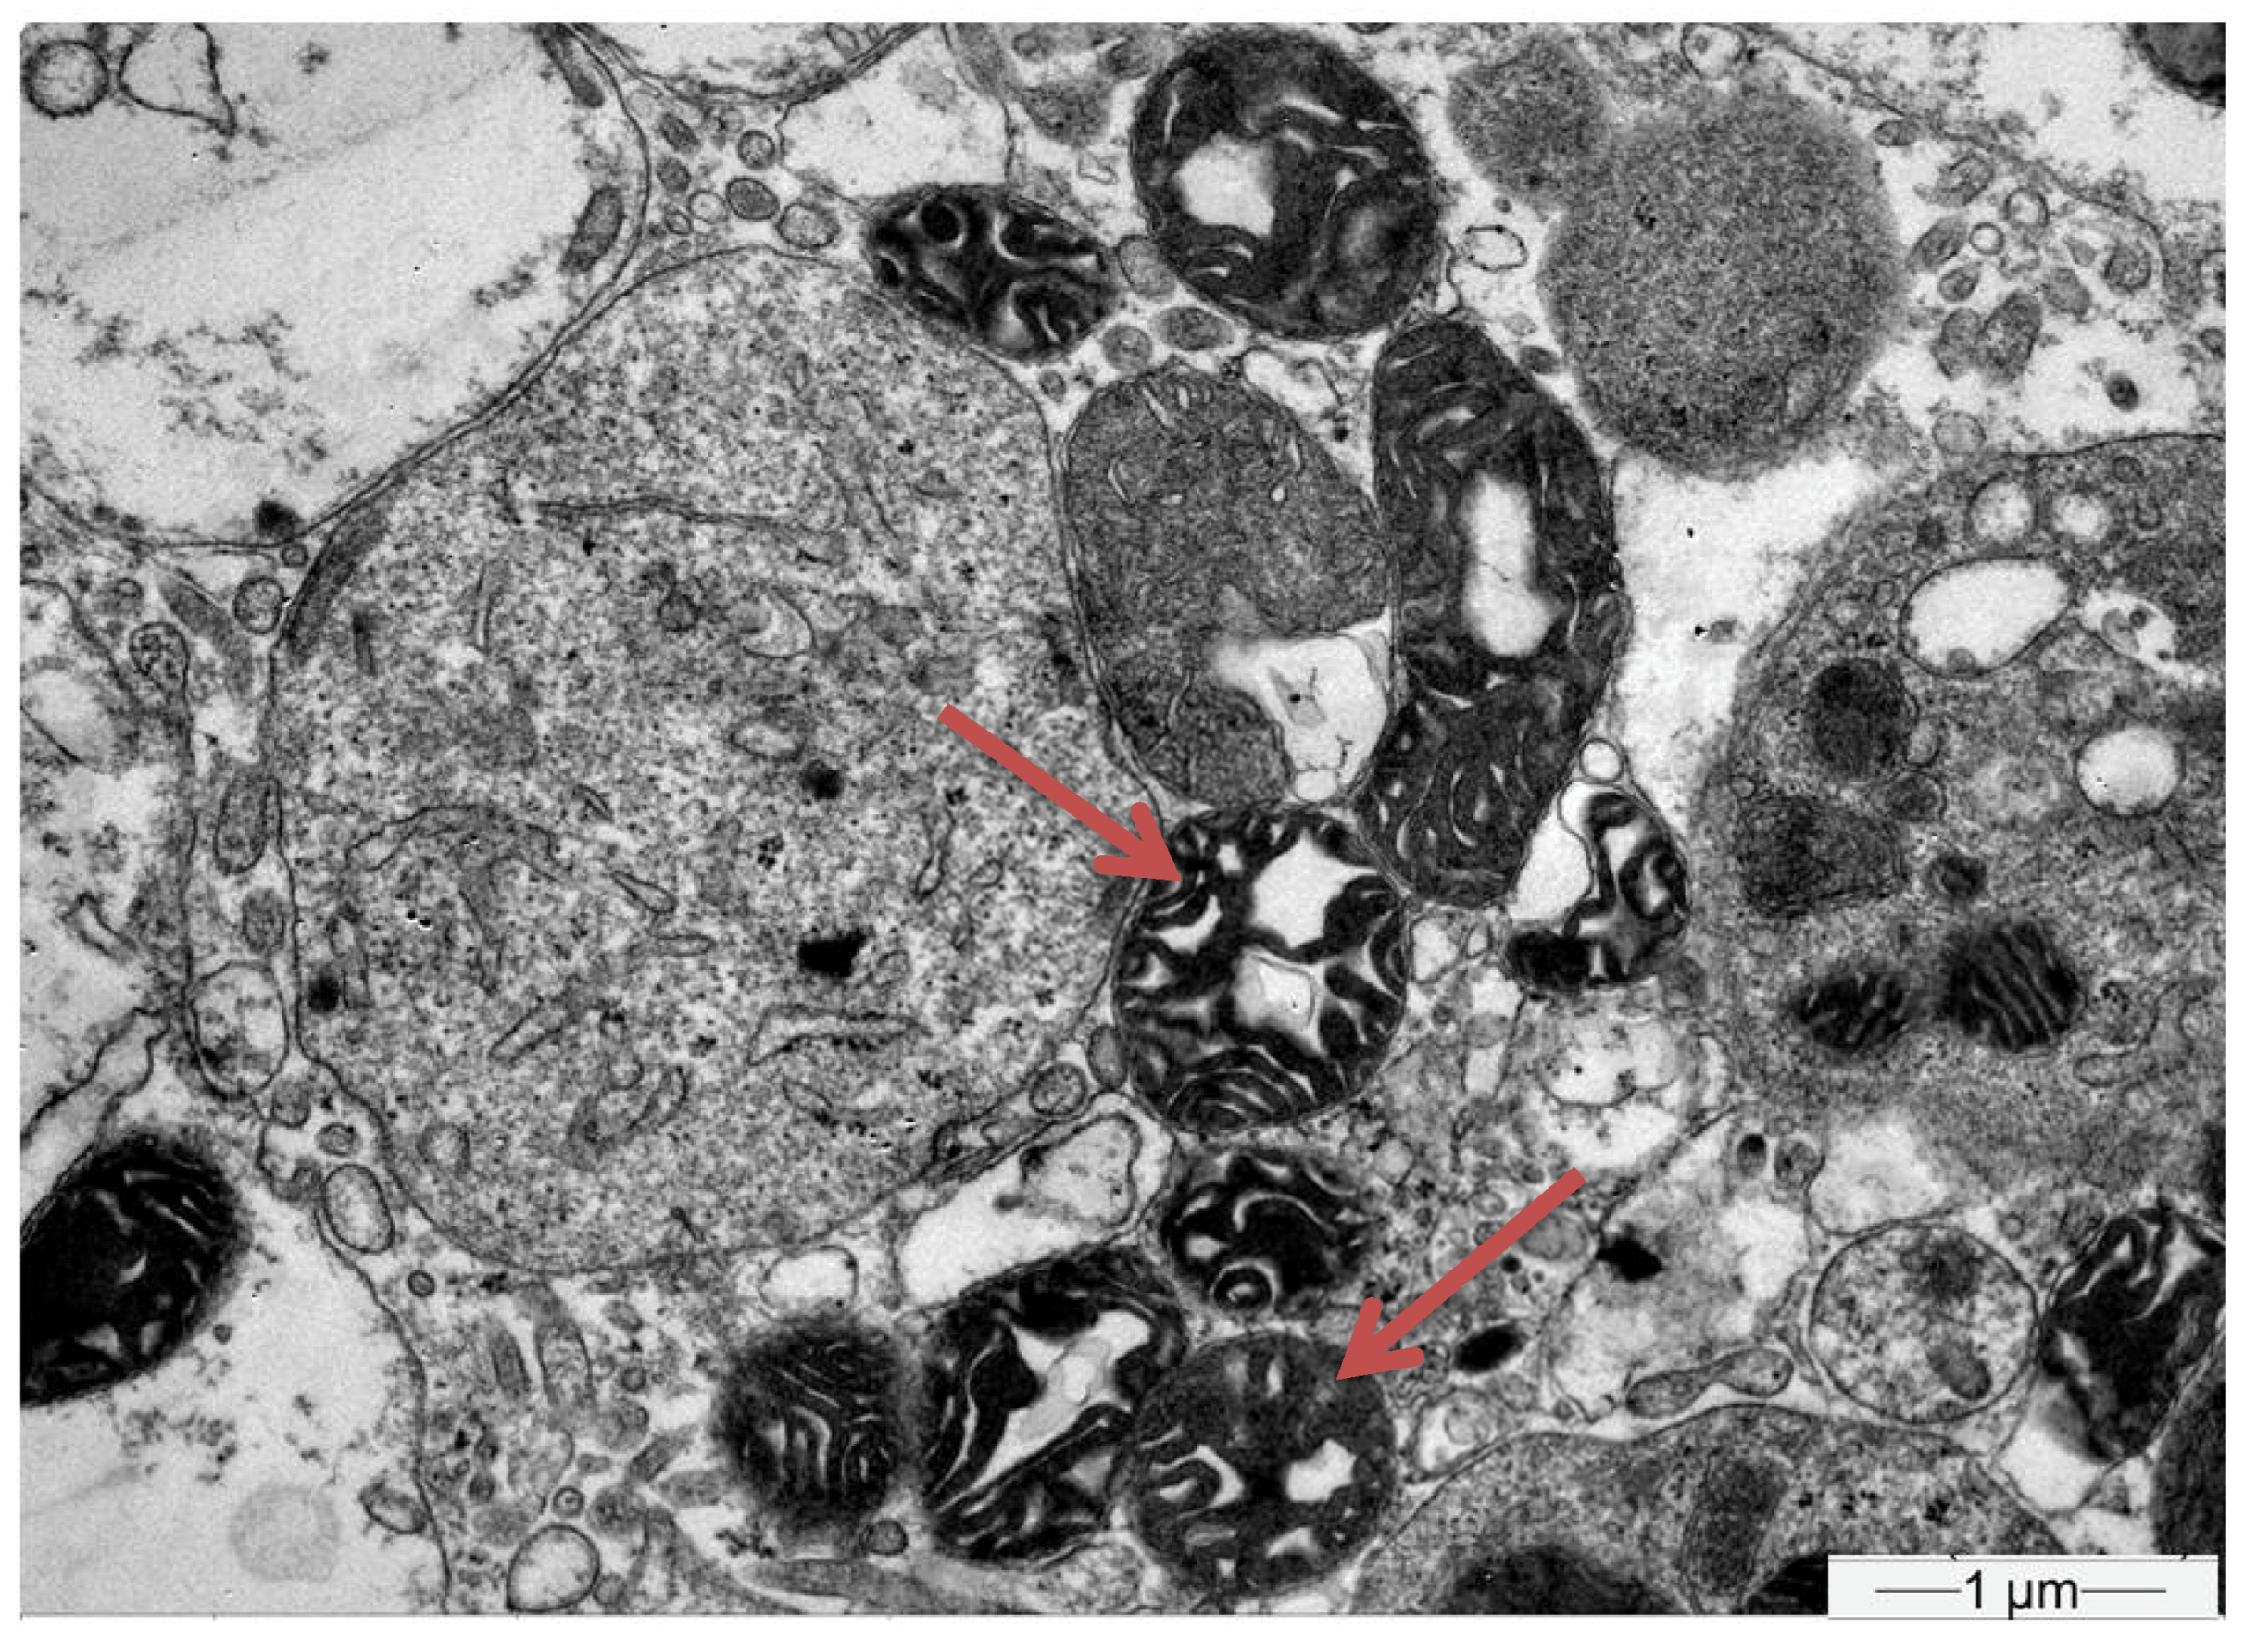

- Herlitz, L.C.; Mohan, S.; Stokes, M.B.; Radhakrishnan, J.; D’Agati, V.D.; Markowitz, G.S. Tenofovir nephrotoxicity: Acute tubular necrosis with distinctive clinical, pathological, and mitochondrial abnormalities. Kidney Int. 2010, 78, 1171–1177. [Google Scholar] [CrossRef] [PubMed]

| Biopsy | Proximal Tubular Injury | Not performed | Not performed | Not performed | Proximal Tubular Injury |